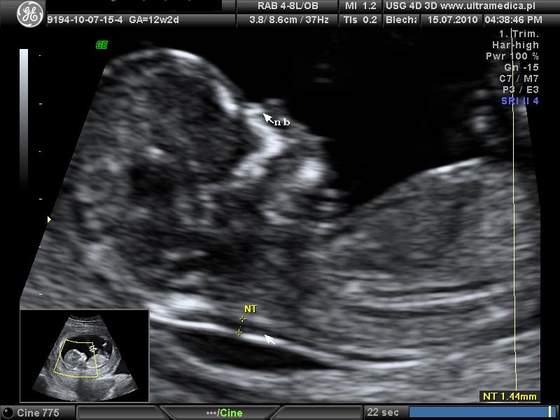

A ja dzisiaj byłam na usg. Okazało sie, ze maluszek jest o tydzien starszy niz na suwaczku, 13t5d, ma 7,7 cm wzrostu

Wrazenie naprawde niesamowite. Na poczatku maluszek spal, pozniej lekarz go budzil mocniej naciskajac brzuch. Zaczal machac raczkami, robic fikołki. Pozniej sie juz uspokoil, zaczal ssac paluszka i dal sie zmierzyc lekarzowi

Takze jestem dumna z mojego dzidziusia. Wszystko jest w porzadku wrecz ksiazkowo. Dostalismy kilka zdjec i płyte CD. Oczywiscie byl ze mna narzeczony. A co najlepsze znamy płeć

a oto ON: